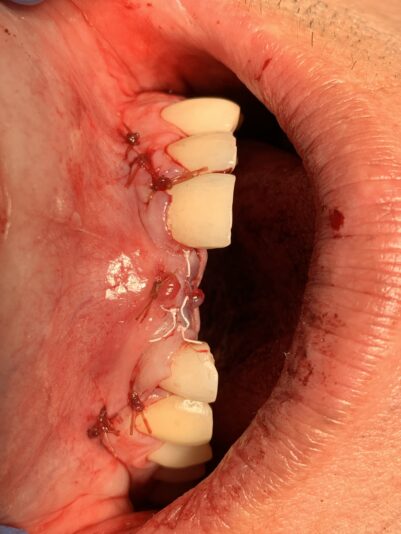

• What in the Trauma is going on? Ok, you all wanted implants and bone grafting so here ya go…

This was a challenging case to say the least, especially when it’s your mother. She fell and fractured 3 of her front teeth amongst other things. A few hours later I had 3 teeth extracted, extracted sockets grafted, ridge augmentation complete, 8…